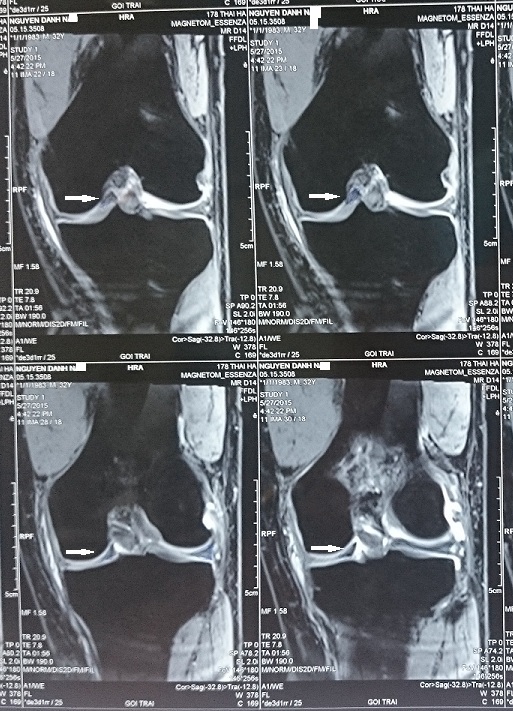

Dấu Hiệu 2 Dây Chằng Chéo Trước(Double ACL)

Dấu hiệu 2 dây chằng chéo trước (double ACL): một dấu hiệu hiếm gặp của tổn thương rách sụn chêm quai va li (bucket handle tear of meniscus)     Nhắc đến tổn thương rách sụn chêm quai va li, có lẽ tất cả các phẫu thuật viên làm phẫu thuật nội soi khớp gối […]